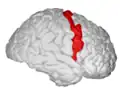

Precentral gyrus

Precentral gyrus a prominent gyrus of the frontal lobe

The precentral gyrus is a prominent gyrus on the surface of the posterior frontal lobe of the brain. It is the site of the primary motor cortex that in humans is cytoarchitecturally defined as Brodmann area 4.

The precentral gyrus lies in front of the postcentral gyrus - mostly on the lateral (convex) side of each cerebral hemisphere - from which it is separated by the central sulcus. Its anterior border is represented by the precentral sulcus, while inferiorly it borders to the lateral sulcus (Sylvian fissure). Medially, it is contiguous with the paracentral lobule.

There is a precise somatotopic representation of the different body parts in the primary motor cortex, with the leg area located medially (close to the midline), and the head and face area located laterally on the convex side of the cerebral hemisphere (cortical homunculus). The arm and hand motor area is the largest and occupies the part of precentral gyrus, located inbetween the leg and face area.